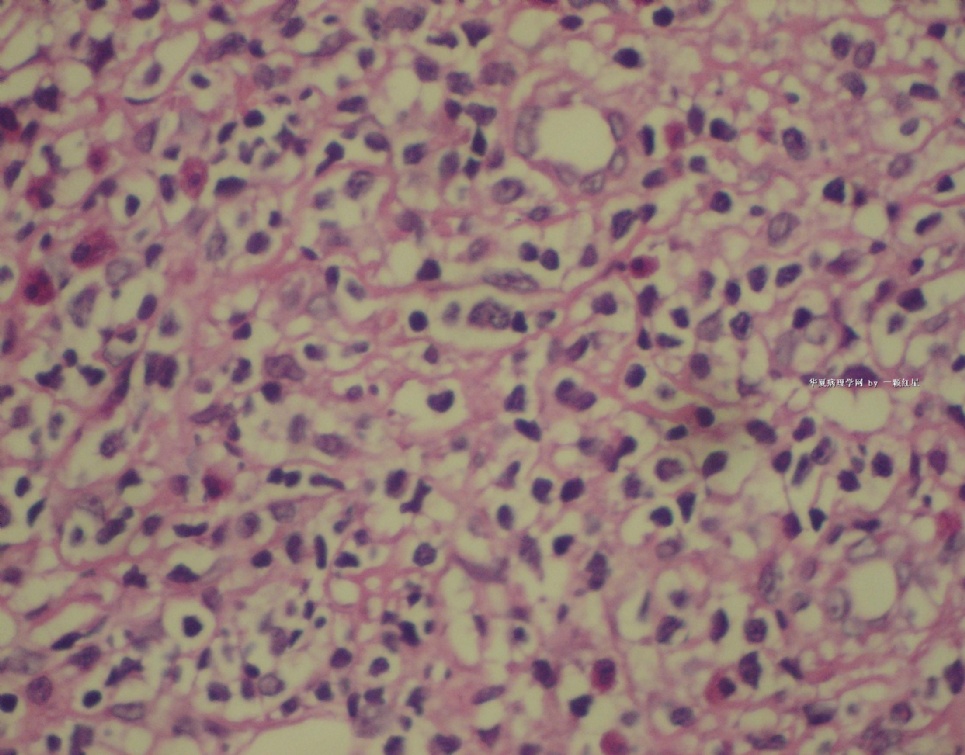

标本名称:  左前臂数个大小不等的皮下肿物。

• 左前臂数个大小不等的皮下肿物     淋巴瘤?图1

图1

病例不错。细胞胞浆透亮,间质血管丰富,图片不是很清晰,似乎有嗜酸粒细胞?

恶性,首先考虑T-NHL。IHC证实。

既往有NHL病史,图片不太清晰,细胞弥漫,胞浆透亮,首先考虑T细胞淋巴瘤。